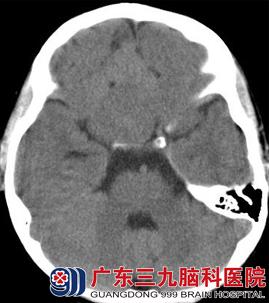

CT表现(图1、2):前颅窝底可见一等密度(与脑实质密度相同)占位性病变,其前方可见囊性的低密度影,与脑脊液密度相似,相邻脑组织受推压,未见明显水肿密度影。MR表现(图3-6):病变呈等T1等T2信号,边界清晰;其前方可见长T1长T2信号影,增强后,病变未见强化。弥散加权成像(DWI):未见病变弥散受限,前方囊性部分呈低信号。考虑为前颅窝脑外占位性病变。

图2 CT平扫:前颅窝底可见一团块状等密度影